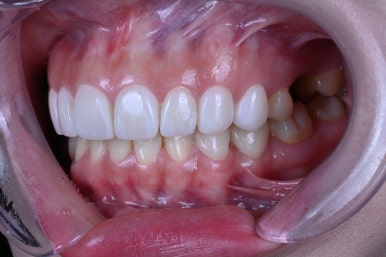

어디에서 보아도 원래 치아의 어두웠던 색상은 보이지 않고,

치아가 너~무 말 이빨처럼 커보이지도 않고, 자연스러운 생김새를 갖고 있습니다.

아래 치아와 비교해보시면 더욱 더 뚜렷한 색상차이를 확인하실 수 있죠.

입안에 위치하고, 눈코입과 함께 보면 요 색상이 꽤나 자연스러움을 아실 수 있으실겁니다.

피부색도 중요한 요소이기에, 이것까지 캐치해서 퍼스널 컬러에 맞는 라미네이트를 제작해드려야 자연스러움의 정점에 이를 수 있습니다!!